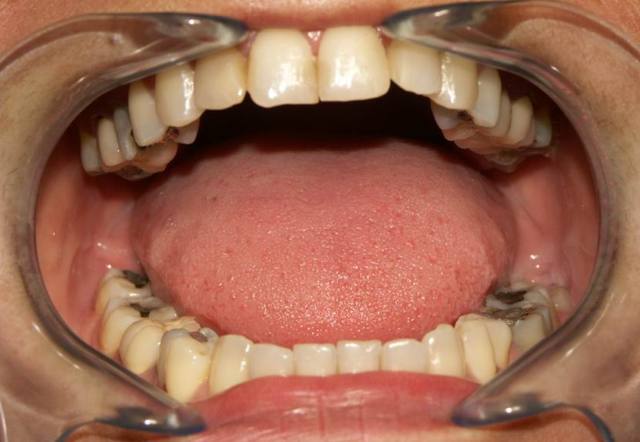

Si vous permettez je commence ça tombe bien je voulais poster ce cas dans les cas cliniques, mais vu que le problème est surtout occluso. Voilà

Patient 45 ans bruxisme, douleurs masseters.

Les points noirs sont les contacts en PIM.

Je précise je fais partie des non-initiés,